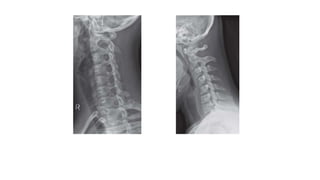

• Normal cervical spine.

• Five lines

• A : the anterior longitudinal

line

• P: Posterior longitudinal line.

• These run along the margin of

the anterior and posterior

longitudinal ligament.

• L is the spinolaminar line,

which runs between the

anterior margin of the dorsal

spines, outlining the posterior

margin of the spinal canal.

• The asterisks represent the

spinous line, along the

posterior margin of the dorsal

spines.

• F is the posterior pillar line,

along the posterior margins of

the articular pillars

• Normal cervicalspine. • Five lines • A : the anterior longitudinal line • P: Posterior longitudinal line. • These run along the margin of the anterior and posterior longitudinal ligament. • L is the spinolaminar line, which runs between the anterior margin of the dorsal spines, outlining the posterior margin of the spinal canal. • The asterisks represent the spinous line, along the posterior margin of the dorsal spines. • F is the posterior pillar line, along the posterior margins of the articular pillars